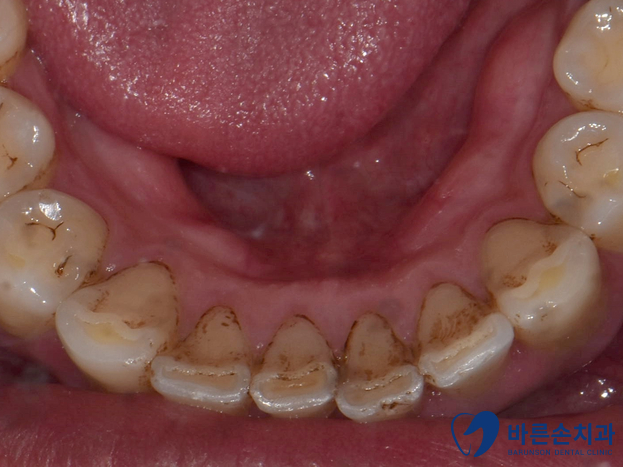

신곡동치과 치석제거를 받기 전 후 사진입니다.

사진에 보이는 것처럼 스케일링 하기 전,후 차이가 많이 나죠??

치아 주변으로 누런 치석이 보이실겁니다.

제거 후 피가나는 이유도 이런 치석으로 인해 잇몸이 좋지 않았기 때문이에요..

보통은 아래 앞니 안쪽에 치석이 많이 쌓이게 되니까

칫솔을 세로로 세우셔서 안쪽을 닦아주셔야해요.